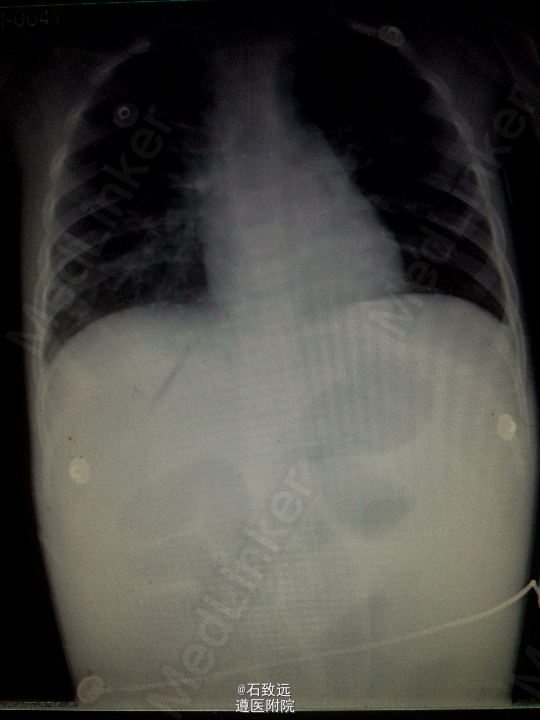

入院考虑:新生儿便血原因待查:新生儿自然出血症? 处理:予禁食水,补液,止血治疗。20h后患儿哭闹,出现腹胀,腹壁发红发亮,叩腹呈鼓音,肠鸣音弱。腹平片示:腹胀气,肠梗阻? 予胃肠减压后体温恢复正常,腹胀明显改善。入院后第15天给予开奶,患儿再次出现腹胀,禁食灌肠后腹胀缓解。行下消化道造影提示:先天性巨结肠。遂转外科行手术治疗,行“巨结肠根治术”。术后继续予补液、抗炎、抗感染、禁食水等对症处理,病情逐渐稳定。现患儿治愈出院。 出院诊断为:新生儿先天性巨结肠合并坏死性小肠结肠炎。